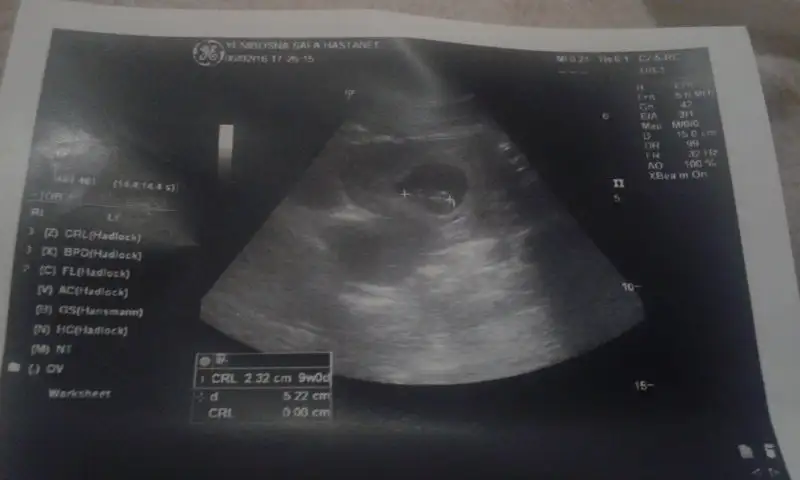

Bu da diğer bebeğimin. İkiside karından :)

O 9 haftalık buda 7 haftalık